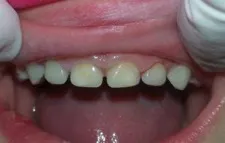

Leigh was three-years-old when he first came to my office with failed restorations and rampant caries (figure 1). He had come from overseas where both he and his mother had bad experiences with dentists and developed severe dental phobia. His mother was delighted to see that her children did not scream during treatment in our office.

Figure 1: Child presents with failed composite restorations and rampant caries.